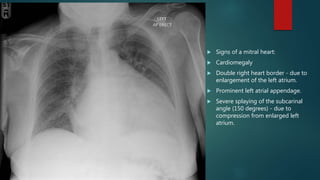

 Signs of a mitral heart:

 Cardiomegaly

 Double right heart border - due to

enlargement of the left atrium.

 Prominent left atrial appendage.

 Severe splaying of the subcarinal

angle (150 degrees) - due to

compression from enlarged left

atrium.